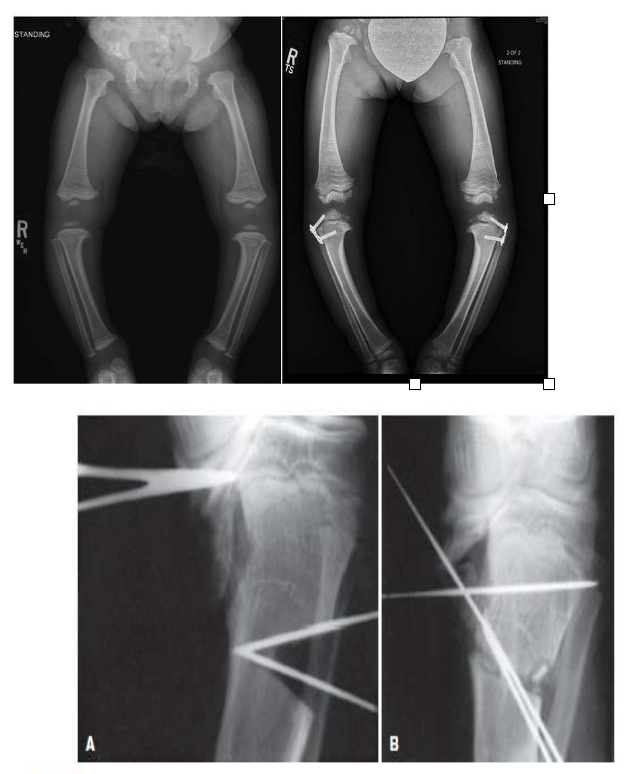

Điều trị bệnh Blount phụ thuộc vào tuổi trẻ và mức độ vẹo trong. Thường với trẻ 2-5 tuổi, chỉ cần theo dõi hoặc thử đeo nẹp nhưng với biến dạng tăng tiến thường cần phải phẫu thuật chỉnh xương.

Khi gối vẹo trong nặng kèm xoắn vặn xương chày vào trong nhiều, góc trục đầu và thân xương chày trên 11 độ, có thể dùng nẹp Denis Browne với bàn chân xoay ngoài và dạng chân. Nẹp thường mang ban đêm không quá 3-6 tháng để chỉnh xoắn vặn xương chày vào trong quá mức.

Ở trẻ lớn với gối vẹo trong nặng làm lệch trục cơ học của chi dưới, đôi khi cần phải phẫu thuật làm dính đầu sụn tăng trưởng của đầu dưới xương đùi/đầu trên xương chày hoặc chỉnh xương chày khi xương đã trưởng thành.

Sau phẫu thuật: có thể cần bó bột hoặc nẹp để bảo vệ xương lành, bệnh nhân cần tập tầm vận động và làm mạnh cơ chân.